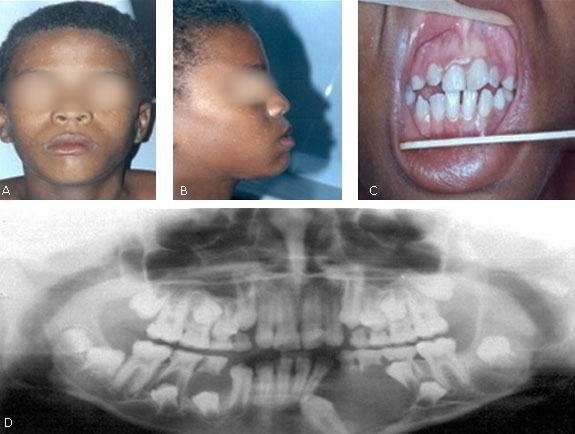

Durante a anamnese e história médica pregressa, não relatou qualquer alteração sistêmica e nenhuma informação relevante da história familiar. Ao exame físico geral foi observado aumento de volume no lado direito da face, hipertelorismo, base nasal larga, bossa frontal (Fig. 1, A), leve prognatismo mandibular (Fig. 1, B) e dedos dos pés encurtados.

Ao exame físico intrabucal, paciente na fase de dentadura mista com presença de dentes deslocados de posição e desvio de linha média (Fig. 1, C). Foi realizada inicialmente a radiografia panorâmica (Fig. 1, D) e observaram-se áreas radiolúcidas bem definidas, uni e multilobulares com halo radiopaco na mandíbula e maxila. Na região posterior da maxila do lado esquerdo encontra-se uma área radiolúcida unilocular associada ao germe unidade 28, na região de mandíbula do lado esquerdo, observa-se uma área radiolúcida unilocular associada à unidade 38, outras áreas radiolúcidas são identificadas ipsilateral, uma área radiolúcida unilocular e multilobular associada ao germe da unidade 33 que se encontra impactado, estendendo-se para a região de pré-molares e outra mesial à unidade 37. No lado direito da mandíbula encontra-se uma área radiolúcida envolvendo o germe da unidade 44 (Fig. , 1D).

Fig. 1 - (A): Visão Frontal: demonstrando a presença de hipertelorismo, bossa frontal e base nasal larga. (B): Norma lateral: evidenciando leve prognatismo mandibular, (C): Dentes deslocados de posição e desvio da linha média. (D): Radiografia panorâmica evidenciando múltiplas lesões radiolúcidas associadas a dentes retidos. Fevereiro/2004.